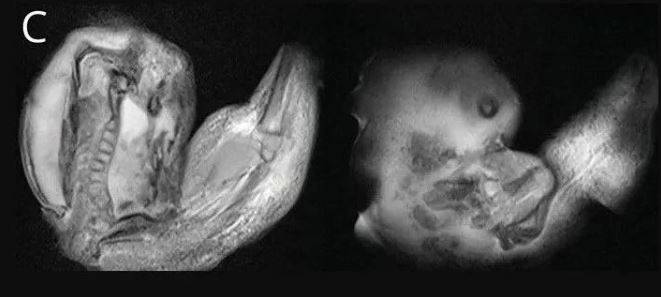

Körpənin kəllə sümüyünün gözlənildiyindən daha geniş olduğu və hərəkət problemi olduğu üçün xəstəxanaya gətirildiyi bildirilib. Hərəkət bacarıqları; iməkləmə, ayaqda durma, yerimə, qaçma, yellənmə, dönmə, yuvarlanma, atlama və tarazlıq kimi hərəkətləri təmin edir. Körpənin kəllə sümüyünü müxtəlif görüntüləmə üsulları ilə araşdıran tədqiqatçılar onun beyninin sıxıldığını və maye yığıldığını aşkar ediblər.

Əlavə müayinə nəticəsində məlum oldu ki, körpə hələ ana bətnində olarkən əkizi olub, lakin ikinci körpə kifayət qədər inkişaf edə bilməyib və körpənin kəllə sümüyünün içərisində ilişib qalıb.

Nəticədə kifayət qədər inkişaf etməyən bu embrion digəri tərəfindən saxlanılıb. Əməliyyatdan sonra bir yaşlı qızın vəziyyətinin necə irəlilədiyi barədə məlumat verilməyib.